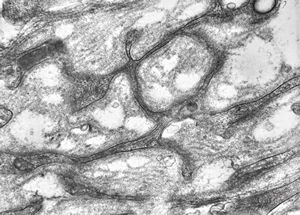

F,23y. | n.suralis - hypertrophic demyelinating neuropathy [onion bulb]